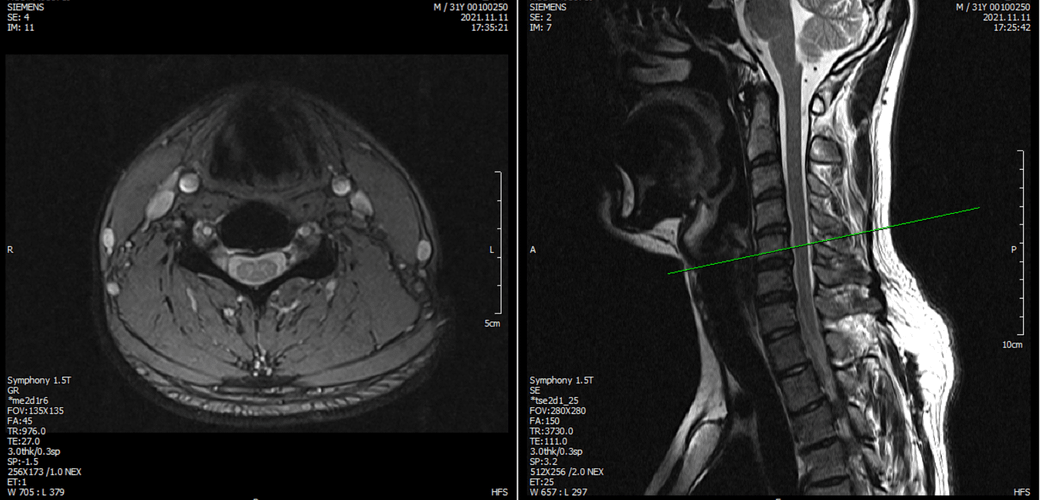

※우리들병원 (신경외과 대표원장) : 경추,요추 MRI 촬영했고 요추는 매우 건강하고 경추에는 일자목에 퇴행성 디스크가 보이지만 한쪽팔에 저림이나 힘빠짐을 유발할 정도는 절대아니고, 다른 원인을 찾아야한다고 했습니다.

※분당서울대병원 재활의학과 : 근전도검사 이상없음, 경추 요추 MRI를 봐도 근골격계 문제로 보기 어렵다. 신경계 문제도 아니다.

※분당서울대병원 신경과 : 근전도에 경추,요추,뇌 MRI를 다 했으니 할만한 검사는 다했고, 디스크가 아예 없는 것은 아니기 때문에 디스크 증상일 가능성이 있음, 주사치료 받아보는 것 권유, 과반사(DTR항진) 있으나 정상범주.

3명이 디스크가 아니라고 하는데 1명이 디스크일수 있다고 하니까 조금 어렵습니다. 경추디스크가 약간은 있으니 팔저림은 설명할수 있다해도 다리저림은 설명이 안됩니다.. MRI 결과상 요추는 매우 건강하다고 하셨거든요.

아래는 저의 경추과 요추 MRI 사진 첨부합니다.